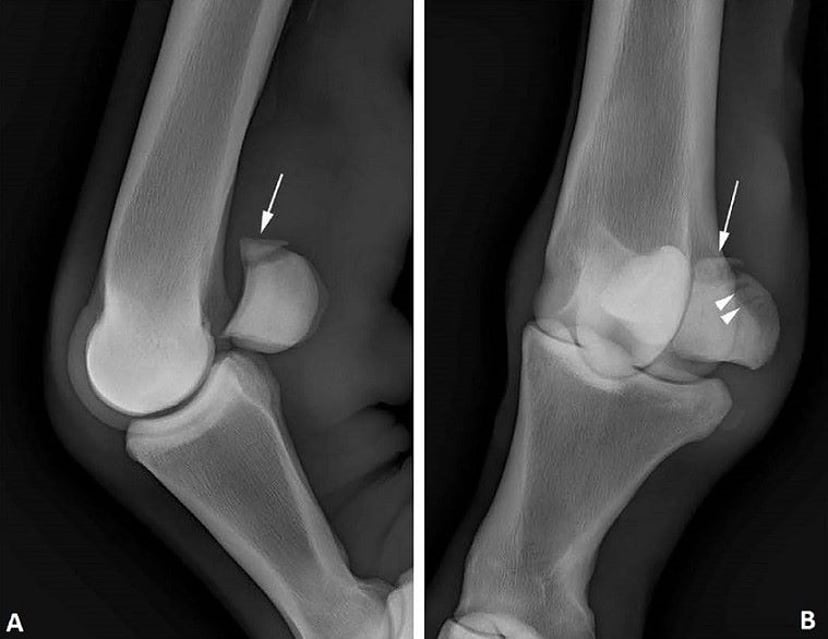

T-LCP Fixation of a cranial mid-body fracture of the axis in an adult horse A Delicate Repair of a Dramatic Equine Skull Fracture Equine Fracture Repair Recovery Time Equine Fracture Repair, 2nd Edition, Wiley-Blackwell Pedal Bone This fully revised Second Edition offers a valuable tool for veterinarians making clinical decisions when faced with horse fractures, covering emergency care and splinting, the most current innovative techniques in equine fracture repair, and new implant systems